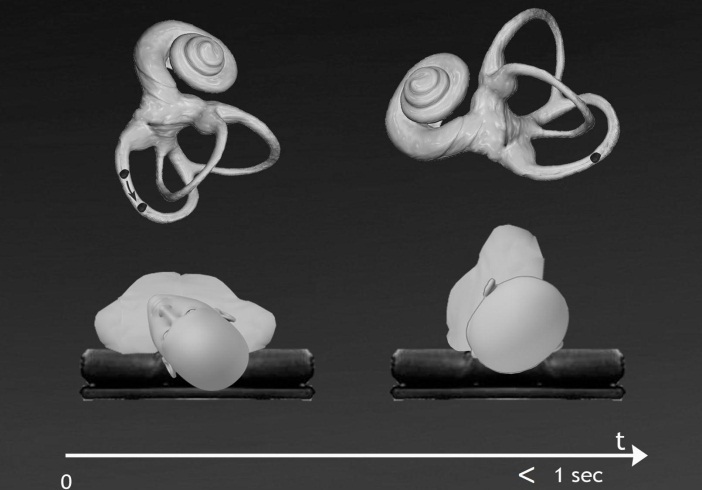

The aim of the present study is to evaluate through a controlled, randomized, double-blind study the short-term (one hour) efficacy of QLR compared with a "fake QLR" which does not cause a significant shift of otoliths from the position in which they are located after the Dix-Hallpike Test (DHT): therefore, the “fake-QLR” (Figure 2) can be considered a sham-maneuver with a possible placebo effect.

Figure 2.The “Fake-QLR” maneuver for left posterior canal BPPV

The sham maneuver (Fake-QLR) consisted of the rapid rotation of the head by about 90° in the supine position from the Dix-Hallpike position triggering signs and symptoms of posterior canal BPPV to an ipsilateral nose-down position in less than 1 second.